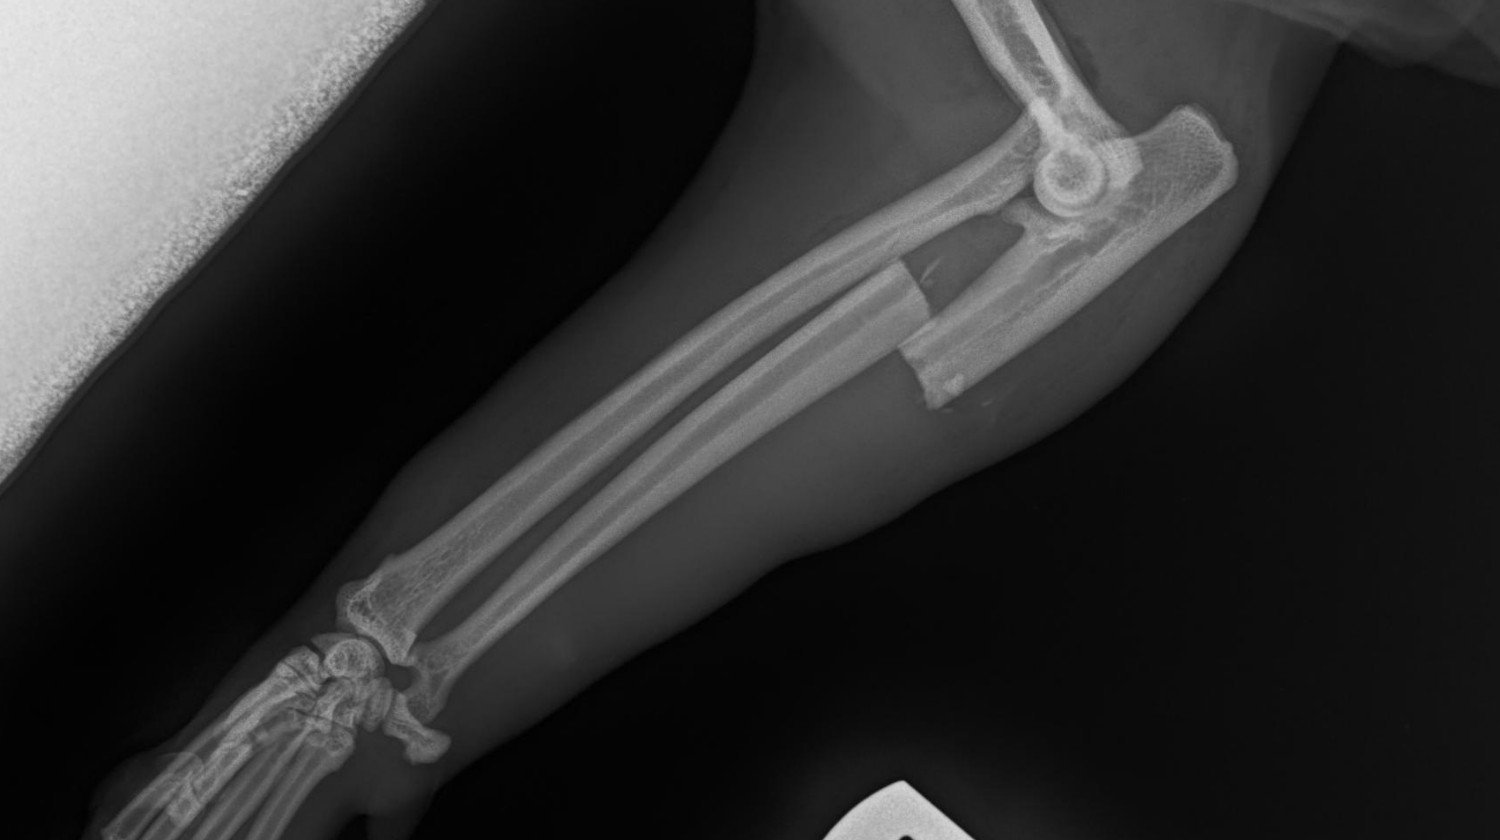

Benek je mamin kocúr a minulé leto sa mu stala hrozná nehoda - bol rozdrvený v automatickej bráne na príjazdovej ceste.

Výsledkom boli dve silno zlomené labky, z ktorých jedna bola aj vykĺbená.

Najprv potreboval korekčnú operáciu vykĺbeného kĺbu. Potom sa jedna z jeho rán infikovala, čo si vyžiadalo antibiotickú liečbu. Najnovšie sa mu zlomil jeden z drôtov, ktoré držali kosti pohromade, čo znamenalo, že musel podstúpiť ďalšiu operáciu.